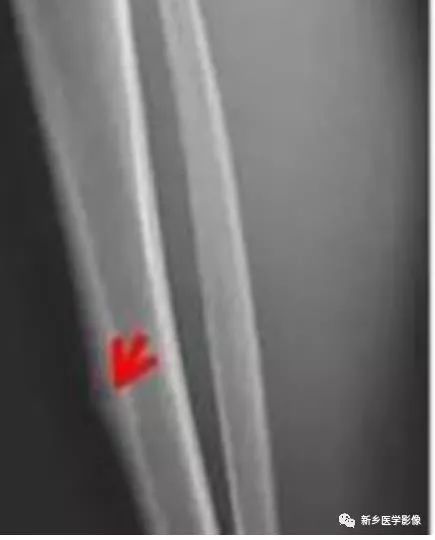

X线片上可分为皮质型,松质型和骨膜下型。

其中皮质型占70%,最常见,多见于长骨骨干。瘤巢靠近骨皮质内面,有小的透射线区域,周围是致密骨,若位于皮质内,则硬化环更明显。反应性增生硬化明显时,可遮盖瘤巢。

松质型:最常见于股骨颈,其次是手足的小骨和椎体,瘤巢位于骨端或不规则骨,周围硬化不明显,可仅有骨硬化边,病灶周围常无 新骨形成,但有密度增加的骨环包绕病灶。

CT/平片上,“瘤巢”周围多出现反应性骨质增生硬化:松质骨增生硬化或骨膜反应